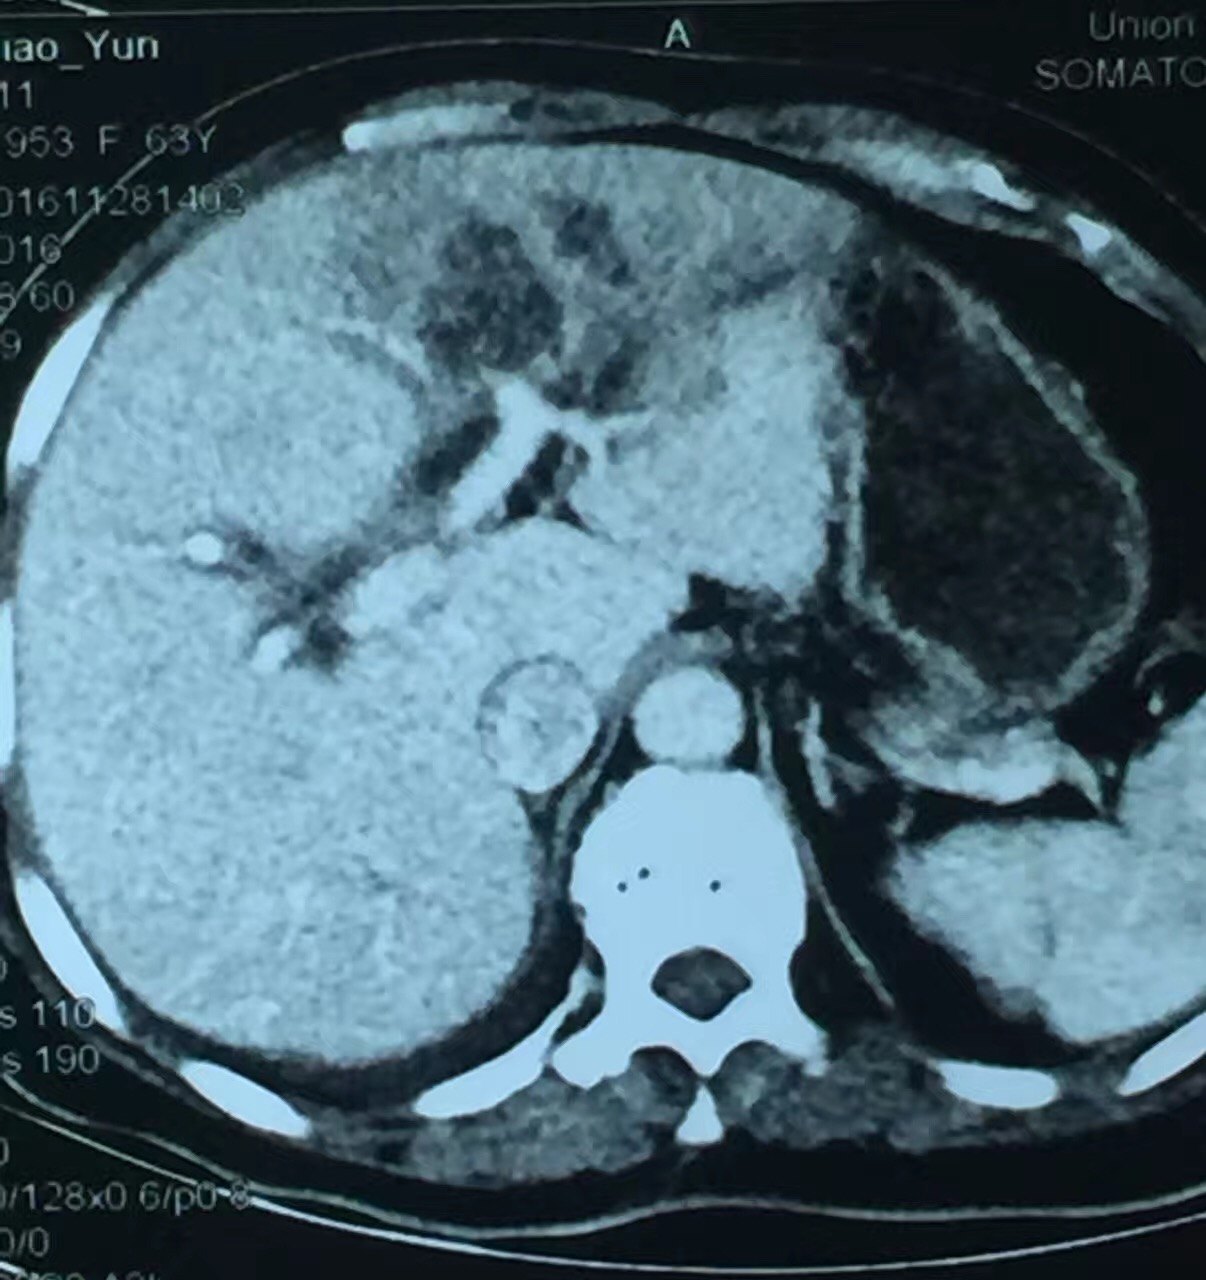

弥漫性脂肪肝伴正常肝岛一例ct增强病例

增强扫描,肝岛表现与脂肪浸润区同步均匀强化.